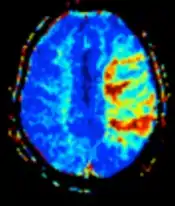

| Diffusion weighted (DWI) | Conventional | DWI | Measure of Brownian motion of water molecules.[78] | High signal within minutes of cerebral infarction (pictured).[79] | ![]() |

| Perfusion weighted (PWI) | Dynamic susceptibility contrast | DSC | Measures changes over time in susceptibility-induced signal loss due to gadolinium contrast injection.[84] |

|